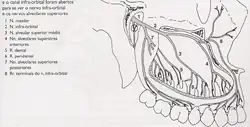

Nervo Maxilar

- Nervo infra-orbital: Seus ramos mais periféricos transmitem mais sensibilidade geral das regiões da pálpebra inferior, asa do nariz, lábio superior e gengiva vestibular dos dentes anteriores e prémolares.

- Nervo Alveolares superiores anteriores: Dentes incisivos e caninos superiores.Processo alveolar; periodonto, gengiva.

- Nervo alveolar: Inverna a polpa e periodonta dos dentes prémolares e eventualmente a raiz mesiovestibular do primeiro molar superior.

- Nervos alveolares superiores posteriores: Inervam a polpa e periodonta dos dentes molares superiores.

- Nervo palatino maior: Transmite a sensibilidade proveniente da mucosa do palato duro desde a região do canino até o limite anterior do véu palatino.

- Nervos palatinos menores: Palato mole.

- Nervo nasopalatino: Proveniente da mucosa da região anterior do palato duro, compreendida entre canino e incisivo central e da mucosa da região anterior do septo nasal. No seu trajeto, o nervo nasopalatino alcança a fossa incisiva, atravessa o forame incisivo e percorre o septo nasal em direção superior e posterior até o teto da cavidade nasal.